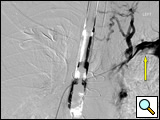

Diagnosis starts with a physical exam with a particular emphasis on the head and neck area. Chest x-ray may show a hilar mass in the case of an obstructing bronchogenic carcinoma or mediastinal mass (e.g. lymphoma) or mediastinal calcification (e.g. histoplasmosis). Infused computed tomography of the head and neck and chest with a venous phase will show characteristic pictures of numerous superficially draining contrast-filled venous collaterals (Figure 1). It will allow assessment of the mediastinum and help exclude compressive masses in the case of an externally compressive hilar or anterior mass, or exclude extensive intravascular clot secondary to a pacemaker electrode. It will also help determine the patency of the jugular and subclavian veins.

Figure 1: Infused CT scan demonstrating extensive contrast filled superficial venous collaterals (yellow arrow) overlying the right hemithorax and a small contrast-filled "trickle" draining centrally into a clot-filled superior vena cava (blue arrow).